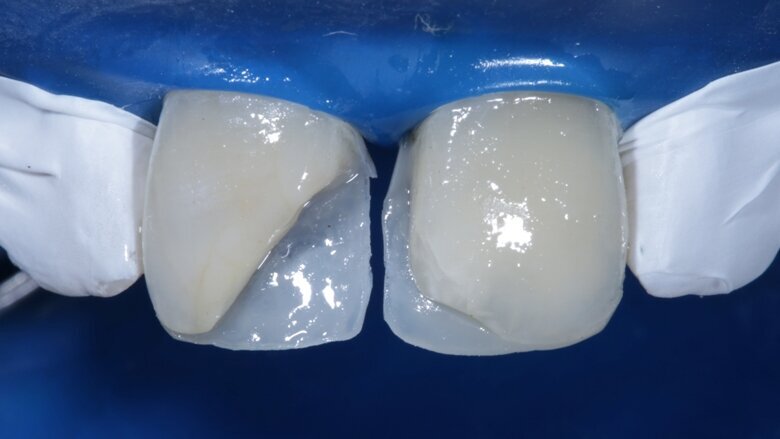

Desaturation was achieved by layering a deeper darker dentin [ A3 Dentin - Fig 12 ] inside and a lighter dentin [ A2 Dentin - Fig 13 ] shade over it in the shape of three mamelons. Incisal Halo was achieved by layering an Achromatic Enamel [clear translucent] shade around the mamelons [ Fig 14 ] and the A2 dentin shade on the incisal edge [ Fig 11 ]. Final layer of A2 Enamel shade was used covering the restoration in 0.5mm thickness so as to avoid too much translucency [ Fig 15 ]. Finishing and polishing were done using the 3M Soflex discs and spirals [ Fig 17 ] as recommended by the manufacturer.

Fig 11 Dentin shade placed incisally for incisal halo effect

Fig 12 Dark dentin shade layered

Fig 13 light dentin shade placed above dark dentin

Fig 14 translucent shade placed in between mamelons

Fig 15 Final enamel layer